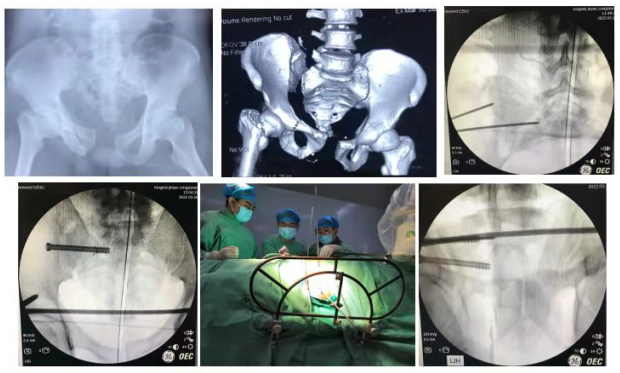

骨科中心二病区以骨科创伤亚专业为发展方向,不断强化复杂骨盆骨折,髋臼骨折,脊柱创伤、复杂关节内骨折,高龄和小儿骨折等危重疑难病种的诊疗技术。以骨科创伤的临床应用及基础研究为主导,打造地区骨科损伤控制研究专科。